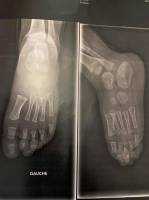

Traitement du pied plat de l'enfant et Syndrome de Déficience Posturale par semelles de type proprioceptives (semelles de postures) à Allauch proche de Saint Julien 13012

Voici les résultats que nous avons obtenu chez un jeune patient que nous suivons depuis un an et pour qui nous avons réalisé, dans notre atelier de podologie à Allauch, une paire d'orthèses plantaires sur mesure de type proprioceptives (semelles posturales)Le patient est un garçon de onze ans que ...